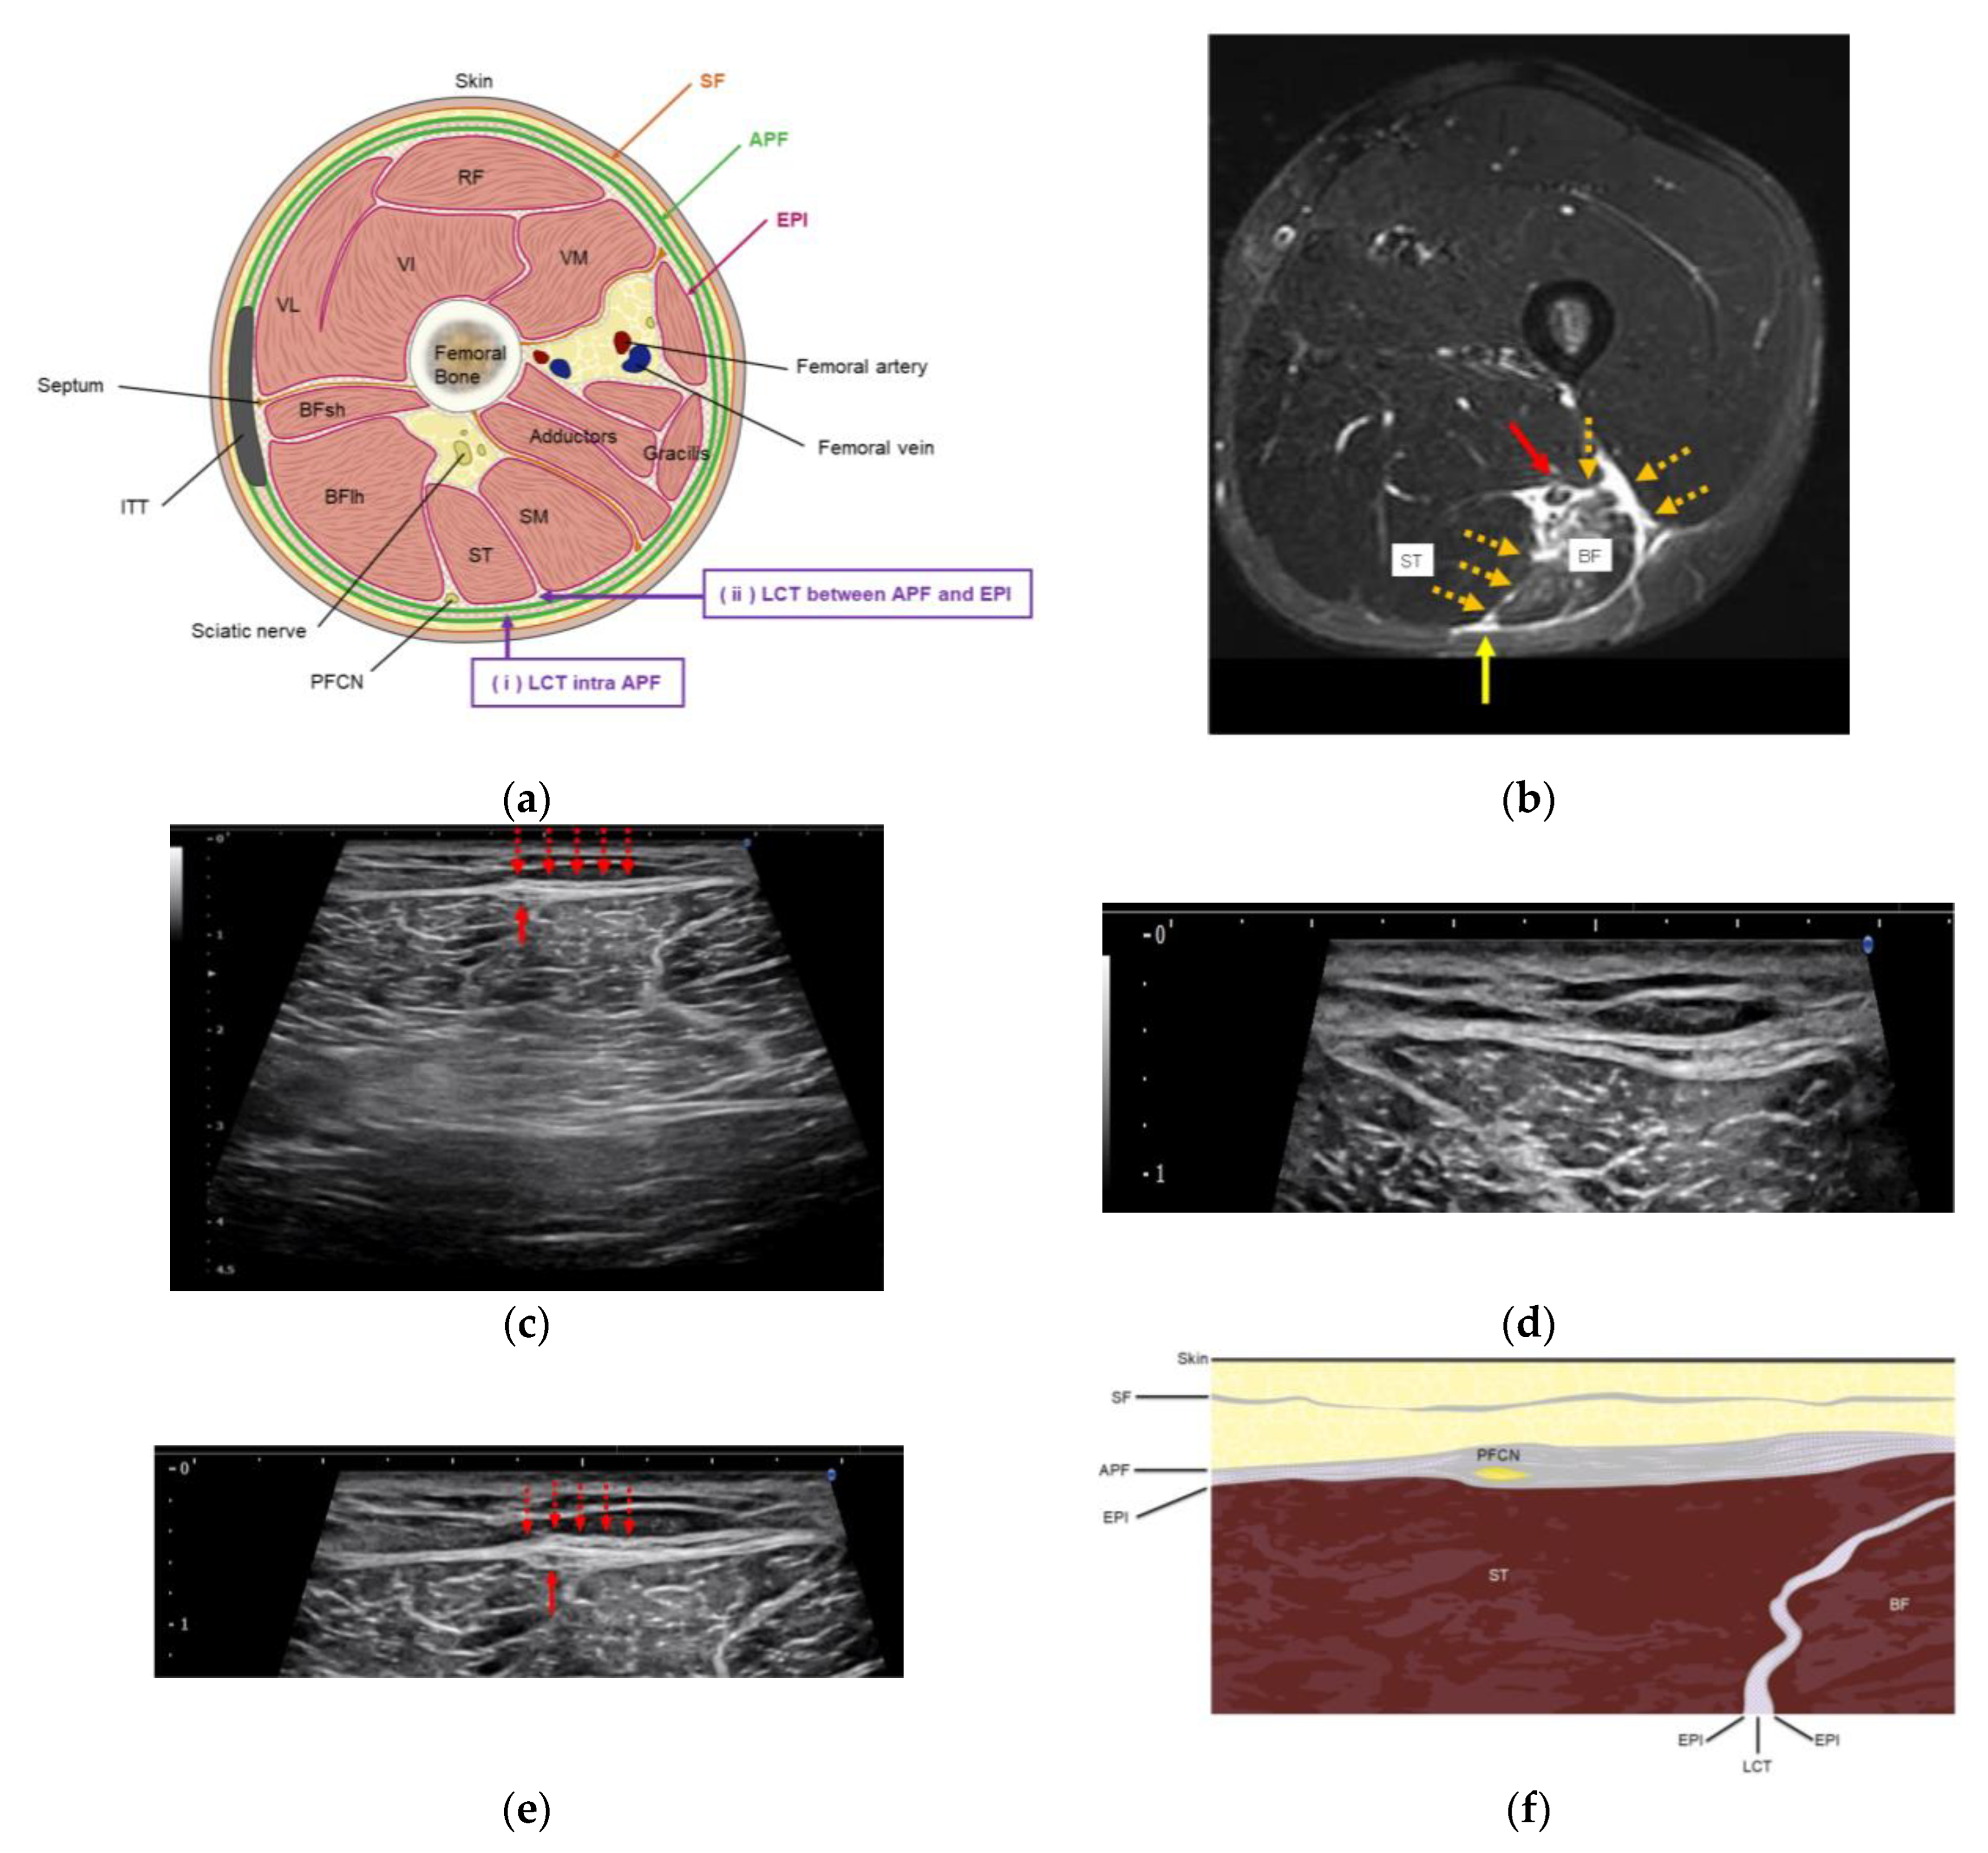

2.4. US Imaging and Sonopalpation

2.5. US-Guided Hydrorelease

3.3. US Imaging and Sonopalpation